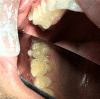

This report illustrates a rare case of a geminated maxillary right second molar tooth using CBCT in a 23-year-old man with severe pain. Nonsurgical endodontic treatment was performed, which gave rise to an asymptomatic tooth at the 12-month follow-up.